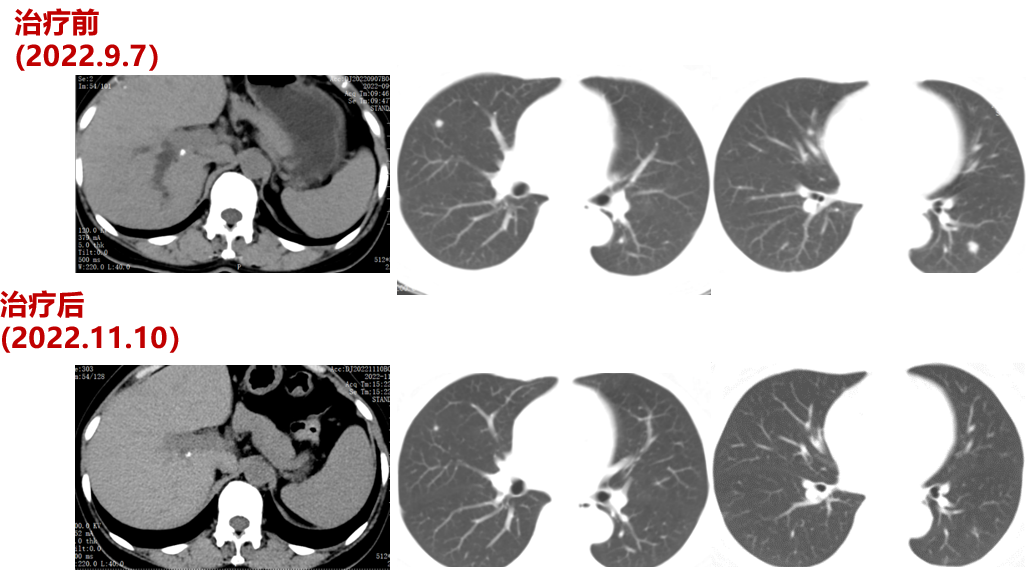

三线治疗(2022-9-7至2023-03-18,PFS:6月余):

2022-09-07至2023-01-03院外使用DS-8201治疗5周期。2周期后疗效评价:PR。CT示:腹膜后淋巴结较前部分缩小;双肺多发转移灶较前缩小。

残余病灶的手术切除:2023-02-22至外院行“左半肝切除术,尾状叶切除术,肝段切除术,胆囊切除术,腹腔淋巴结清扫术,肠粘连松解术,肾周围粘连分解术,肝脏肿物射频消融,肝动脉结扎,腔静脉损伤修复术”。

再次行基因检测,结果提示:HER2扩增倍数为5.49倍

CT(2023.4.14)提示:肾上腺病变较前增大,考虑PD